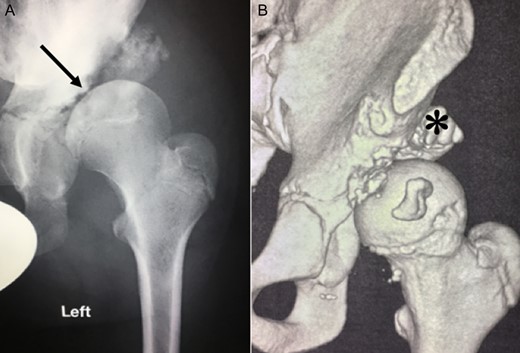

Ten years ago, a 12-year-old male presented to our clinic complaining about limping and massive swelling of the left hip. Figure 1 shows the initial X-ray and the 3D reconstruction of the left hip at first presentation when the femoral head, had already destroyed the lateral edge of the acetabulum like a mortar. Severe pain episodes have apparently not been noticed and a former hip dysplasia was not known. A brief clinical history revealed that the patient presented repeated episodes of finger biting and fevers from 2 to 8 years old. The intelligence level of the patient was at an average. The patient was admitted to a paediatric neurologist and a genetic test. A mutation of the NTRK1 gene was found and the diagnosis of CIPA was established. The right hip initially appeared to be normal and the patient was walking, therefore surgical reconstruction for the left hip was proposed due to massive swelling, inability of normal walking and significant limb length discrepancy. A Tönnis/Kalchschmidt triple pelvic osteotomy with open reduction and a shortening varus derotation osteotomy (VDRO) of the femur was performed (Fig. 2A–B). After 3 months the patient was walking again but another 3 months later the hip dislocated again without severe pain. Although the femoral head was already damaged the hip joint was reconstructed again by open reduction, capsular reconstruction with suture anchors and a trevira tube and a movable external fixator was used to temporary stabilize the joint (Fig. 3). The right hip at this time was still intact and was protected with a pneumatic orthotic device. A few months later in 2009, despite all surgeries, the left hip had entirely lost congruency and the right hip developed subluxation despite conservative treatment (Fig. 4). The patient was still walking so the decision to reconstruct the right hip with open reduction, capsular augmentation with a trevira tube, a triple pelvic osteotomy and VDRO was made (Fig. 5). Few months later this reconstruction failed as well and the hip dislocated without severe pain (Fig. 6).

(A + B): (2008) (A) Hip reconstruction with open reduction, Tönnis triple pelvic osteotomy and shortening rotational varus osteotomy of the left femur demonstrating correct deep reposition in ap view. (B) Lauenstein view shows that the acetabular congruency over the femoral head is restored.